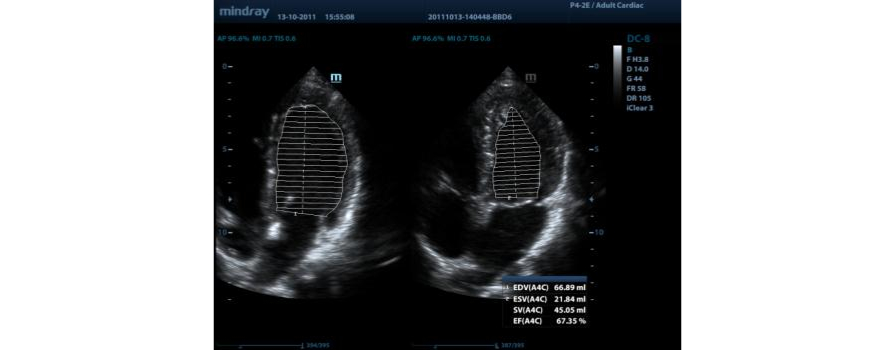

AutoEF

Intelligent way to analyze 2D echo clips to automatically recognize diastole/systole frames and output EDV/ESV/EF etc. results by Simpson method.